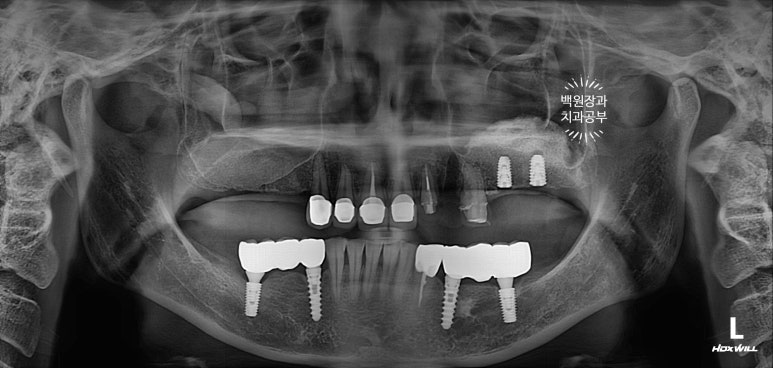

앞니 지르코니아 브릿지와 왼쪽 어금니 임플란트 완성!

앞니 지르코니아 브릿지와 왼쪽 어금니 임플란트가 완성되었습니다.

너무 색깔도 깔끔하게 잘 나오고... 만족스러운데요, 어디가 무엇인지 아시겠어요?

파란색으로 표시된 3개짜리가 앞니 지르코니아 브릿지이고,

보라색으로 표시된 2개짜리가 어금니 임플란트입니다.

앞니와 어금니를 완성해두고 치과용 파노라마 엑스레이를 찍어봅니다.

새로 만들어진 보철물이 경계도 자연스럽게 잘 형성되어있고, 잇몸뼈와 조화롭게 완성이 되었네요.

그리고 오른쪽 어금니 임플란트도 2차수술을 해둡니다.

정말... 다시봐도 상악동 뼈이식술이 아주 적절히 잘 되어 딱 필요한만큼만 되어있네요. ㅎㅎ 이럴때 정말 뿌듯합니다. (변태같나요!?)